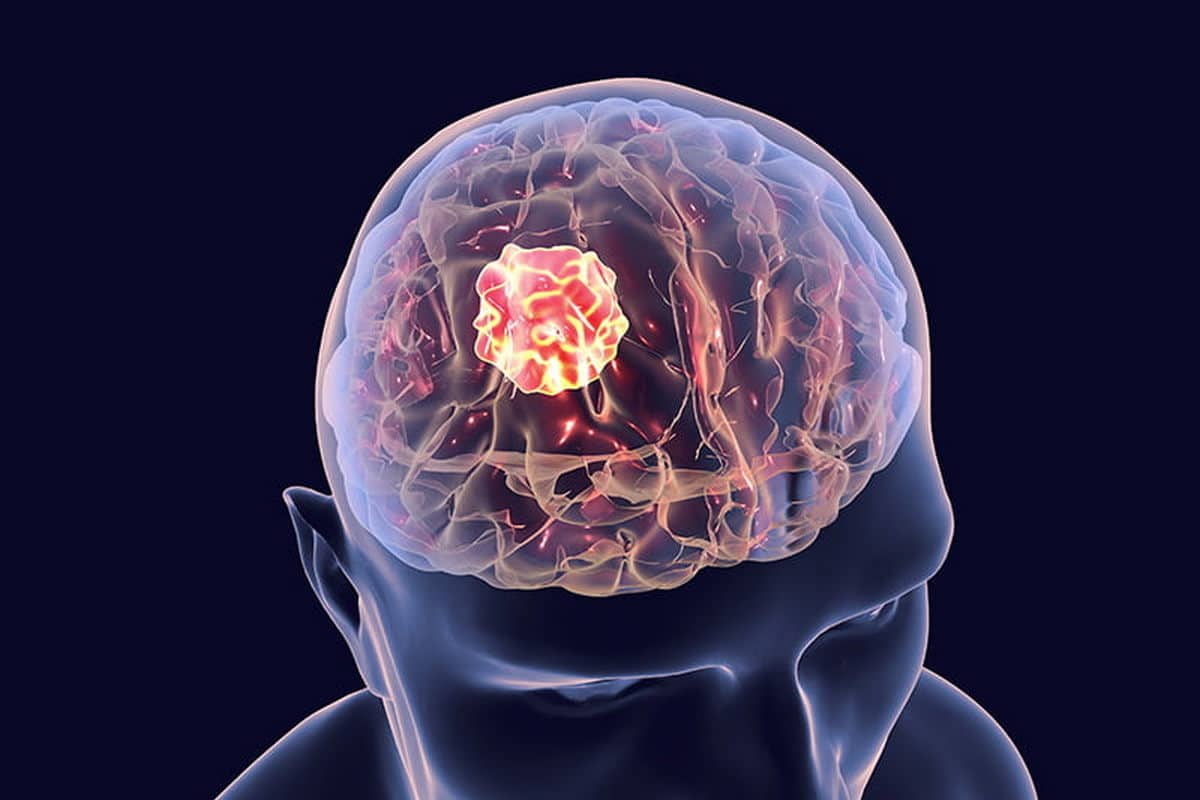

A Salerno parte una raccolta fondi per un dipendente esterno dell’ospedale Ruggi colpito da glioblastoma cerebrale. Servono aiuti per l’intervento al Carlo Besta di Milano e le spese familiari. Lo riporta SalernoNotizie.

Salerno, raccolta fondi per un dipendente colpito da glioblastoma: serve un intervento urgente

Una corsa contro il tempo per sostenere cure urgenti: è stata avviata una raccolta fondi per aiutare un dipendente esterno di una ditta che opera in appalto presso l’Azienda Ospedaliera “San Giovanni di Dio e Ruggi d’Aragona” di Salerno, colpito da glioblastoma cerebrale in stadio avanzato. Dopo gli ultimi accertamenti clinici, per l’uomo si è reso necessario un intervento chirurgico presso l’Istituto Neurologico Carlo Besta di Milano, centro di riferimento nazionale.